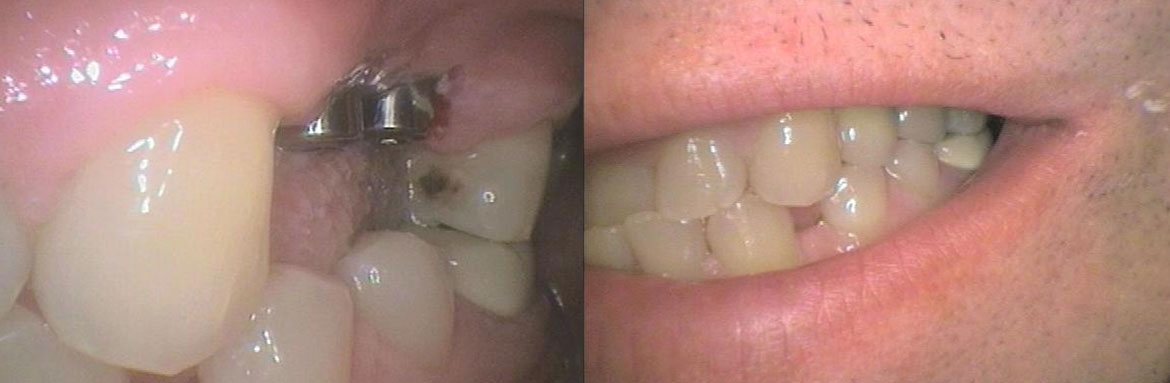

Η απώλεια ενός ή περισσοτέρων δοντιών αποκαθίσταται πλέον με εμφυτεύματα.΄Ολοι λίγο ή πολύ γνωρίζουν πια γι΄αυτά ,αλλά το πόσο εύκολη και προσιτή είναι η τοποθέτηση τους είναι μία απορία πολλών.Κι όμως η διαδικασία τοποθέτησης τους και τα ποσοστά επιτυχίας τους ,σε συνδιασμό με αισθητή μείωση των τιμών τους τα έχουν κατατάξει στις καθημερινές οδοντιατρικές πράξεις.Στο οδοντιατρείο μας τα εμφυτεύματα γίνονται μετά από προσεκτική μελέτη του κάθε περιστατικού ξεχωριστά και με την συνεργασία εξαίρετου συνεργάτη Γναθοχειρουργού.